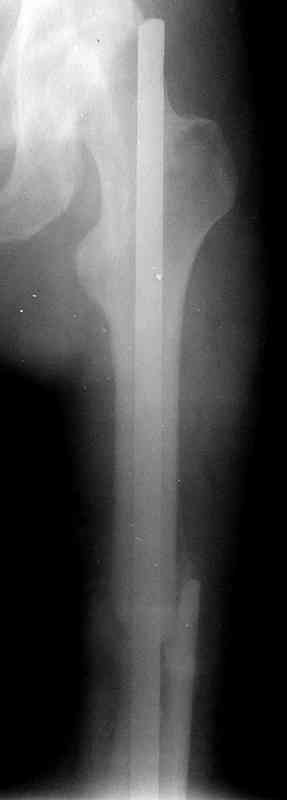

месяцев дистракции укорочение левого бедра удалось полностью устранить. 22.02.00, т.е. через 2 месяца после повторного остеосинтеза, больному произведено дистальное блокирование штифта двумя винтами и демонтирован аппарат Илизарова. В течение 2 недель после операции больной ходил с помощью костылей, потом 2 недели с тростью. Опороспособность и функция оперированной конечности полностью восстановились через 4 недели после операции.

Фиксаторы удалены через 12 месяцев после операции, выполненной по поводу замедленной консолидации перелома бедра с его укорочением.